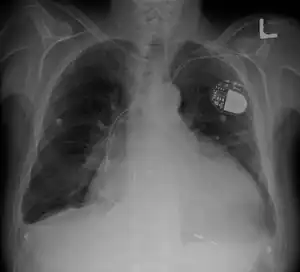

Cardiomegaly on chest X-ray with a pacemaker